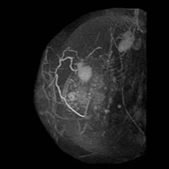

画像中间浅淡白色部分为癌 (治疗前)

治疗6个月后,白色部分变小

治疗一年后白色部分有明显缩小的变化